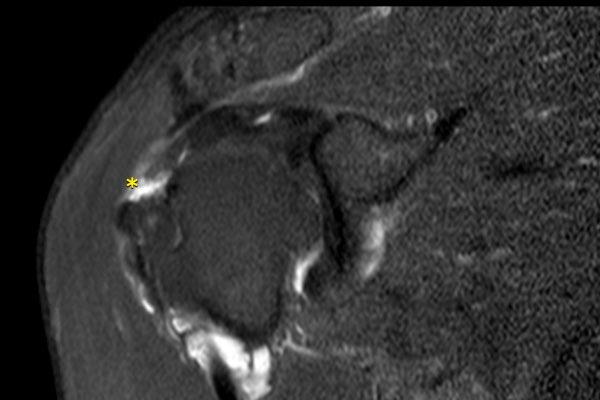

Hình ảnh

Rách gân dưới vai sau chấn thương trực tiếp.

Có hình ảnh co rút gân dưới vai về phía trước kèm phù nề quanh gân trên các chuỗi xung PD-weighted mặt phẳng axial và chuỗi xung T2W xóa mỡ mặt phẳng coronal (dấu hoa thị).

Gân cơ nhị đầu không bị trật (đầu mũi tên).

Bệnh nhân này có tiền sử chấn thương trực tiếp vùng khớp vai phía trước.